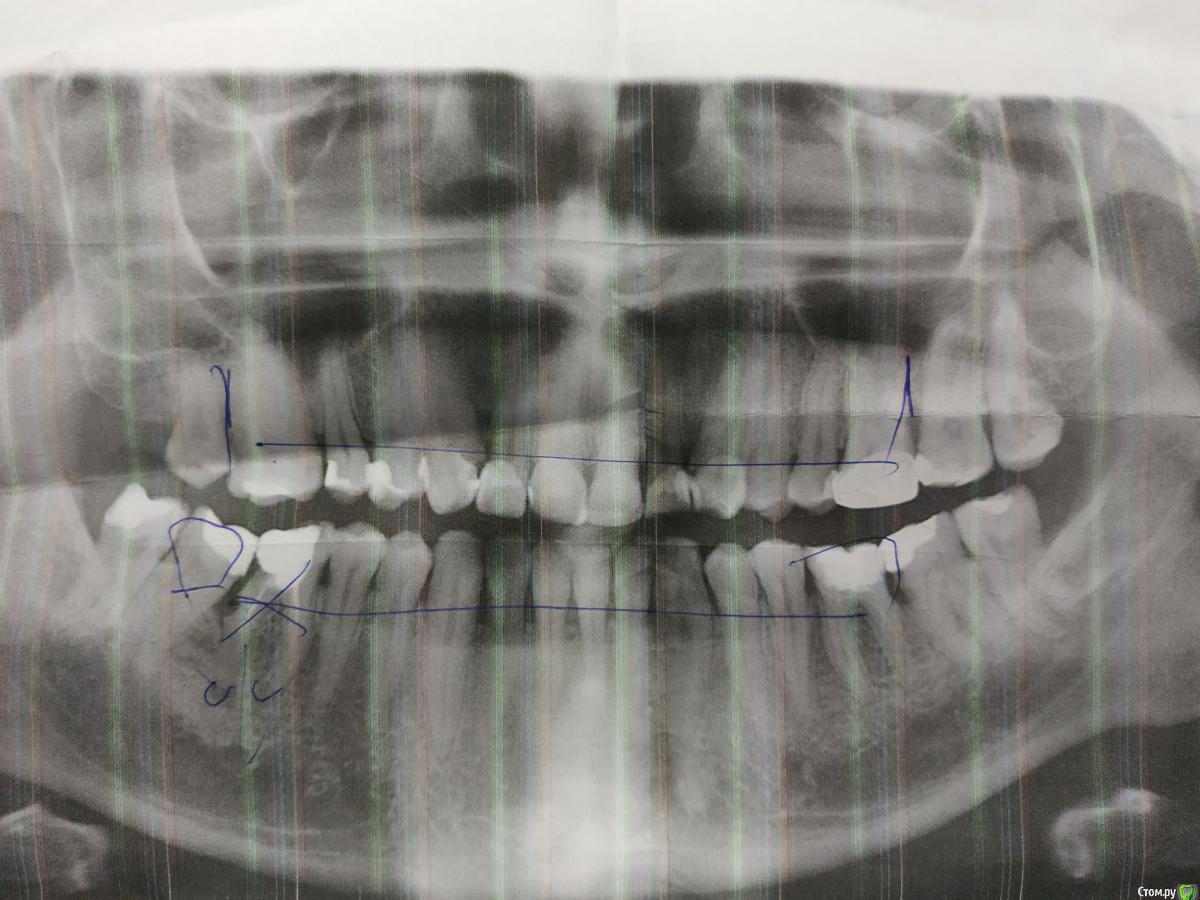

stoch Опубликовано 29 января, 2019 Автор Поделиться Опубликовано 29 января, 2019 (изменено) Доброго времени суток, уважаемые доктора.Сегодня зашел в клинику и сделал снимок, также врач набросал примерную схему лечения, которая займёт несколько месяцев.Будьте добры, если есть свободная минутка, подскажите ваше мнение касательно состояния зубов и выбора метода лечения. Врач в клинике вызывает уважение, четко и по делу, но всё же интересно мнение других профессионалов. Из сюрпризов: нужно удалять один зуб и на его место ставить имплант.Спасибо. Изменено 29 января, 2019 пользователем stoch Ссылка на комментарий

___49___ Опубликовано 29 января, 2019 Поделиться Опубликовано 29 января, 2019 (изменено) нужно удалять один зуб и на его место ставить имплант. - правильно доктор сказал. на счет остального не скажу - более половины снимка не читается(на бумаге , со сгибами и т.д. - вообщем до нас дошли лишь обрывки информации). Изменено 29 января, 2019 пользователем ___49___ 2 Ссылка на комментарий

DmitrySH Опубликовано 29 января, 2019 Поделиться Опубликовано 29 января, 2019 врач набросал примерную схему лечения, которая займёт несколько месяцев. Будьте добры, если есть свободная минутка, подскажите ваше мнение касательно состояния зубов и выбора метода лечения Вам план лечения надо строить с изготовлением диагностических моделей и гипсовкой их в артикулятор. зуб 46 - точно удалять., ОПТГ лучше переделать 2 Ссылка на комментарий

DmitrySH Опубликовано 30 января, 2019 Поделиться Опубликовано 30 января, 2019 Или есть смысл оставить так как есть? У вас же тут не только неудовлетворительный внешний вид.Присутствует стираемость, пломбы в неудовлетворительном состоянии, местами парадонтальные карманы. зуб 46 разрушается. Меня беспокоит вопрос: приобретя хороший эстетический вид зубов в перспективе не станет хуже для их внутреннего здоровья Если все грамотно сделать, то будет только лучше. И конечно от Вас потребуется качественное поддержание гигиены полости рта. 1 Ссылка на комментарий